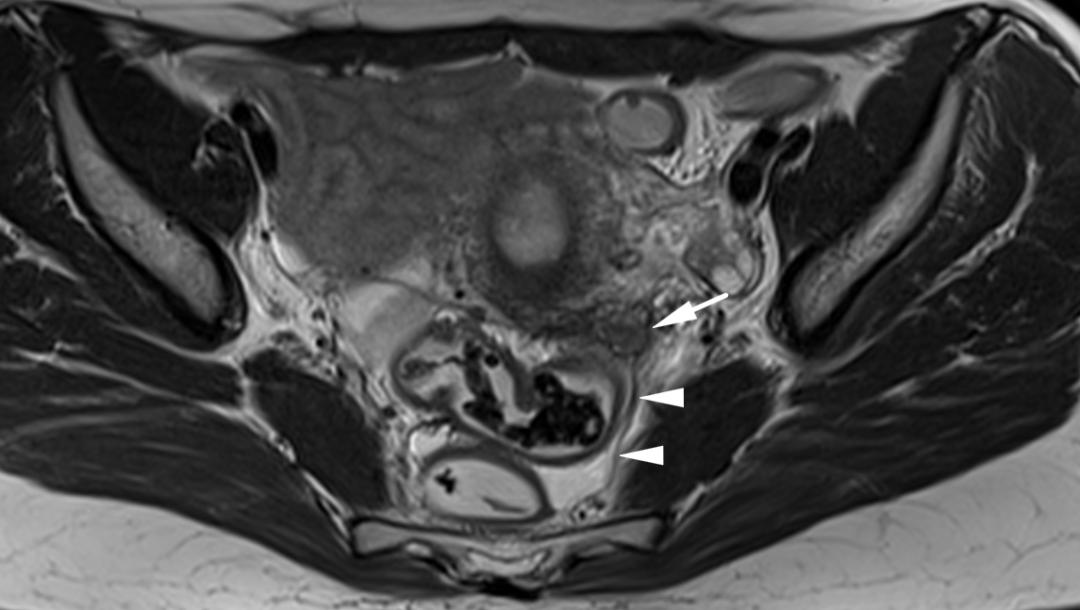

子宫内膜异位至直肠系膜,T2WI 轴位阴道左后方低信号结节,边缘星芒状,累及直肠系膜,但未累及直肠壁。